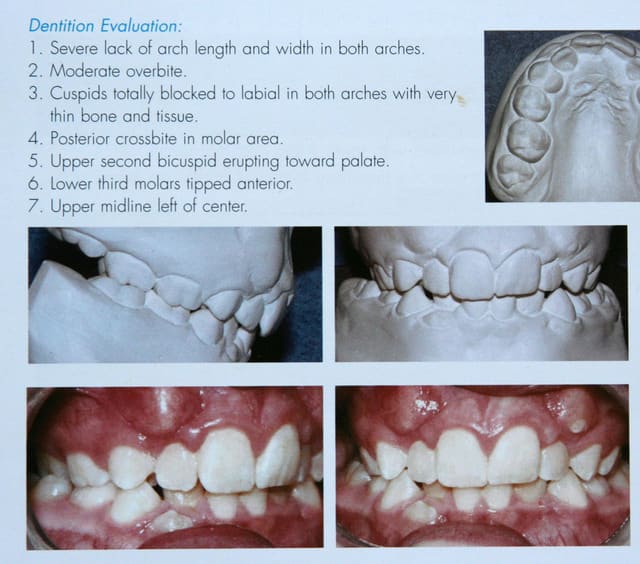

Ce cas, relativement facile à traiter en technique passive,

serait beaucoup plus difficile à traiter en technique bioprogressive.

Exemple du vieil adage :

Pourquoi faire simple quand on peut faire compliqué ?

@+ Bjc.

P.S. : je vous prépare plus difficile.

si je vous ai montré ce cas de D.D.M. c’est afin de vous prouver que les extractions sont de moins en moins nécessaires.

Si j’arrive à le faire, en n’étant ni prof, ni membre de sociétés réputées, c’est qu’avec les techniques actuelles, ce n’est pas très difficile

C’est à la portée de tout orthodontiste